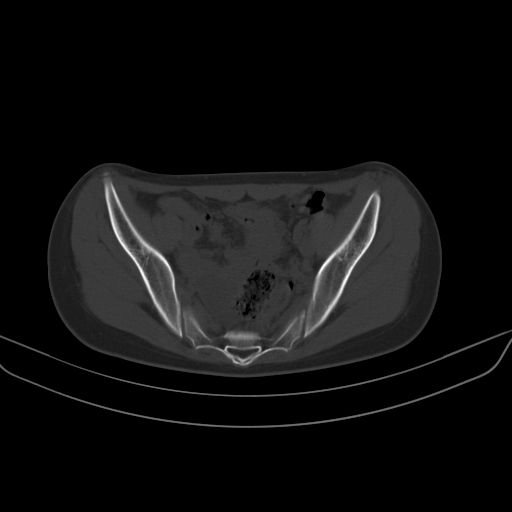

以下是引用zsl6918在2008-7-11 21:40:00的发言:[br]双侧骶髂关节骨质破坏以下三分之一为主,符合强直性脊柱炎表现

以下是引用zhangzhongshou在2008-7-11 21:41:00的发言:[br]患者是女性,hla-b27抗原(—),首先不太考虑强直性脊柱炎,建议查类风湿因子,骶髂关节改变考虑类风湿性关节炎可能性大,建议进一步检查。